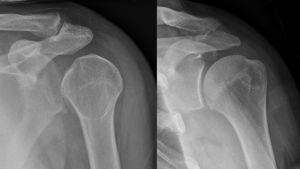

خلع سفلي للذراع بعد حادث سيارة. لاحظ كيفية بروز عظمة العضد. كما يظهر أيضاً كسر في الحدبة الكبرى.

الخلع السفلي هو النوع الأقل شيوعاً، ويحدث في أقل من 1% من الحالات. تسمى هذه الحالة بالخلع المنتصب لأن المصاب غالباً ما يظهر ممسكاً بذراعه إلى الأمام أو إلى أعلى الرأس.[14] يحدث الخلع السفلي بسبب جذب الذراع بقوة مما يجبر عظمة العضد على الخروج من الأخرم.[15] تصاحب هذه الحالة أضرار بالغة في الأعصاب، الأوعية الدموية، أوتار العضلات، الأربطة حسب آلية الاصابة.